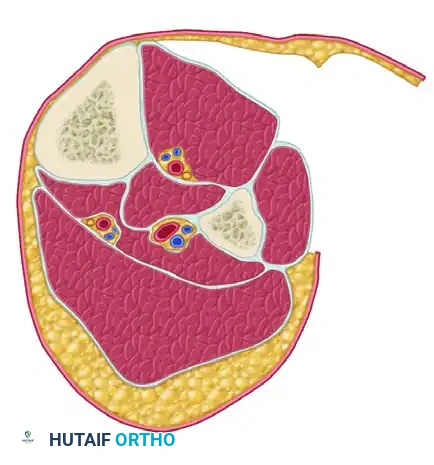

FASCIOTOMY FOR ACUTE COMPARTMENT SYNDROME OF THE THIGH

The thigh is anatomically divided into three distinct compartments: anterior, posterior, and medial. Because the thigh compartments possess a larger volume and greater compliance than those of the leg, thigh compartment syndrome is relatively rare. However, when it occurs, it is typically the result of massive blunt trauma, femur fractures, or prolonged compression.

FASCIOTOMY FOR ACUTE COMPARTMENT SYNDROME OF THE LEG

The lower leg is the most common anatomical site for acute compartment syndrome. It consists of four rigid compartments: Anterior, Lateral, Superficial Posterior, and Deep Posterior.